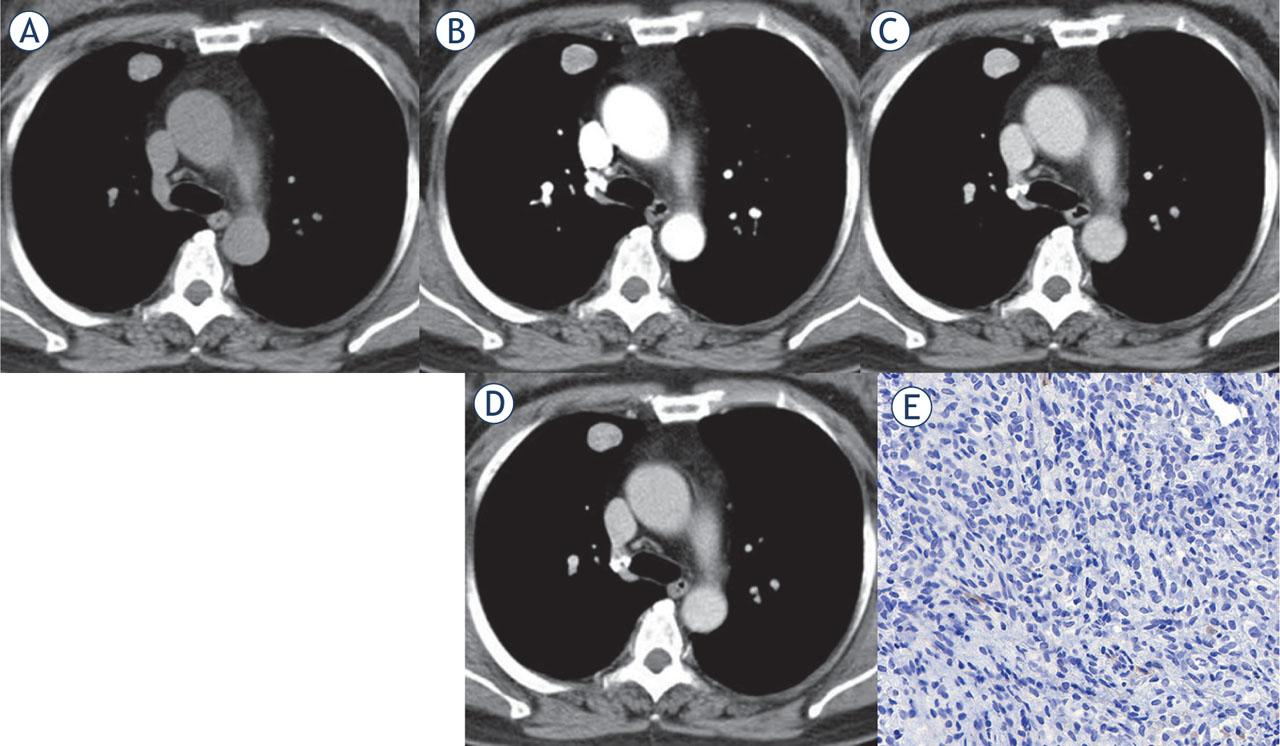

Imaging and clinical comparisons between central and peripheral pulmonary sclerosing pneumocytomas (PSPs)